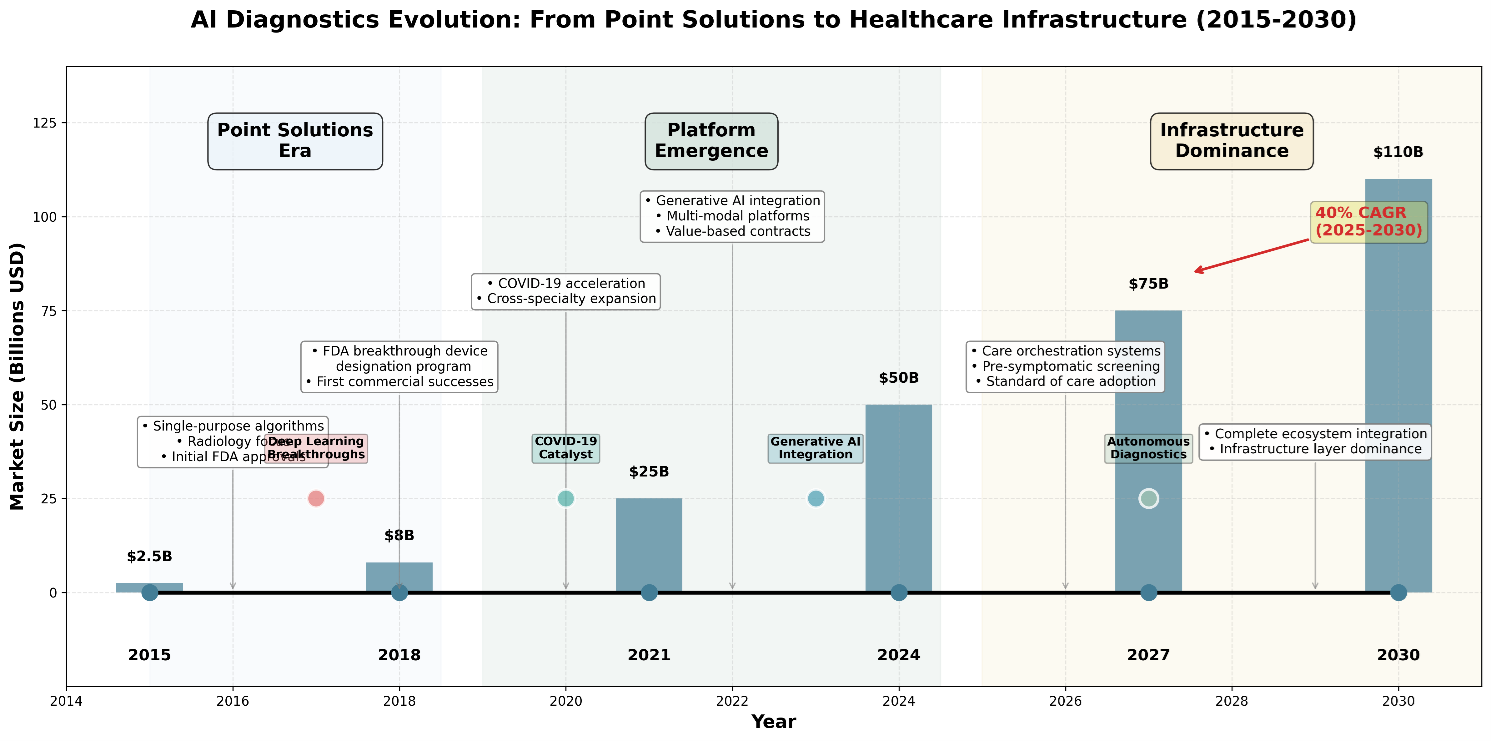

- Massive Market Expansion: The sector is set to grow from $21.66 billion in 2025 to over $110 billion by 2030, driven not by hype, but by structural necessity.

The global AI healthcare market is projected to grow from $21.66 billion in 2025 to over $110 billion by 2030, with diagnostic applications representing a core growth driver. By 2030, algorithmic diagnostic capability will constitute baseline care delivery infrastructure.

Figure 1: Diagnostic AI Evolution Timeline (2015-2030) – The shift from point solutions to infrastructure dominance.

Early activity concentrated heavily in radiology, which served as the initial proving ground. That concentration is visible in sustained growth from the mid-2010s onward, establishing radiology as the foundation layer for clinical AI adoption. More importantly, this early success unlocked confidence, regulatoryprecedent, and workflow acceptance that would later enable expansion beyond imaging.

During the initial deployment phase between 2015 and 2022, these technologies functioned as isolated applications identifying specific pathologies within constrained domains. The current generation represents a qualitative departure. Advanced generative architectures now synthesize disparate data modalities (diagnostic imaging, genetic sequencing, longitudinal health records) into unified stratification frameworks, moving beyond detection toward comprehensive risk interpretation.